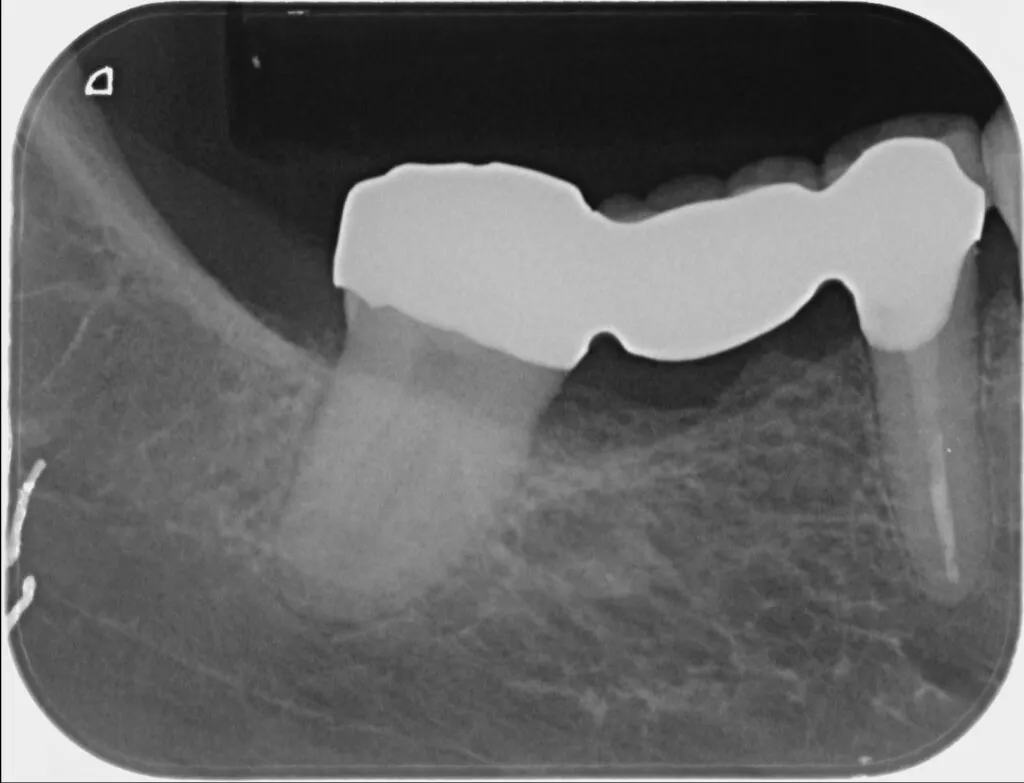

部分矯正は、動かす歯を1本~数本に限定して矯正治療を行うので、短い期間で症状を改善できます。被せものを併用した場合はさらに短期間で治療を終えることも可能です。

隙間があいている前歯を移動させる場合や、傾いている歯をまっすぐに修正する場合に有効な治療法です。またむし歯が骨の中まで進行した場合、通常は歯を抜くことになりますが、歯を引っ張りあげることで、保存できる場合もあります。